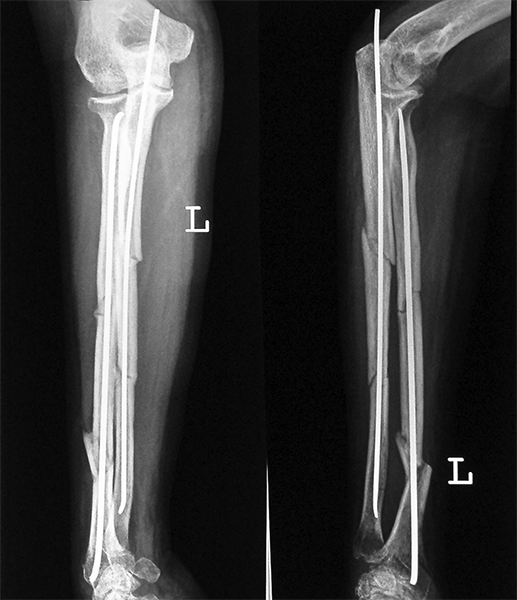

Case:8 Polytrauma

Patient having closed segmented fracture midshaft & lower 1/3 Tibia with closed fracture superior & inferior pubic rami right side with pelvis fracture following vehicular accident wastreated with intramedullary nail for fracture tibia and external fixator for fracture pelvis.

Pre-Op

Immdiate Post-op

Post-op Lateral

Lat-Post Fall

Ex fix with frame

Post-op 1 and half months follow-up

Post Uninon-3Months